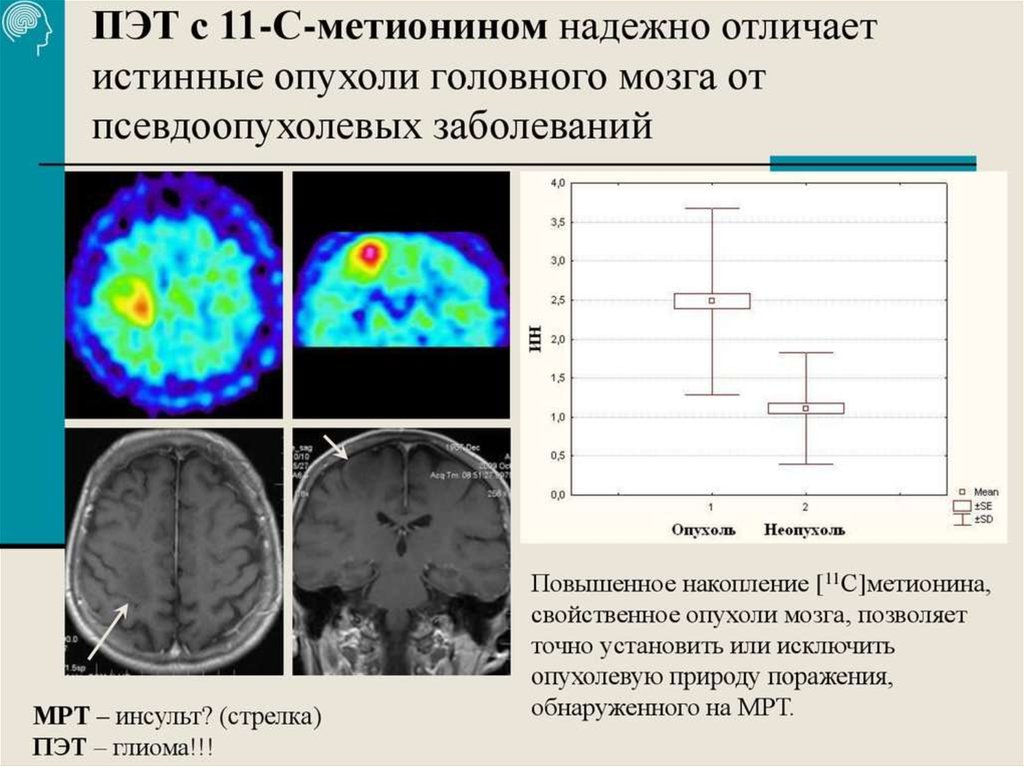

ЭРХПГ при холедохолитиазе заключение. Желчнокаменная болезнь лучевая диагностика. Эндоскопическое исследования механической желтухи. Лучевые исследования при желтухе. Позитронно-эмиссионная томография мозга. ПЭТ кт головного мозга. ПЭТ кт опухоли головного мозга. Позитронно-эмиссионная томография опухоли.

Позитронно-эмиссионная томография мозга. ПЭТ кт головного мозга. ПЭТ кт опухоли головного мозга. Позитронно-эмиссионная томография опухоли. Общие симптомы онкологии. Симптомы онкологических заболеваний. Основные симптомы онкологии. Симптомы раковых заболеваний.

Глиома внутримозговая кт. Метастатические опухоли мозга. ПЭТ кт томограмма. Кт, ПЭТ И ПЭТ/кт. ПЭТ кт с контрастом. Скопление контраста ПЭТ кт.